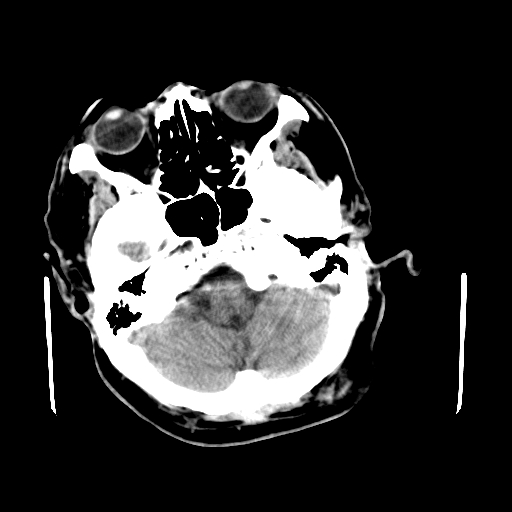

男,62岁,右侧肢体活动障碍不灵活三天,左侧头皮肿物十余年(ct值8hu)。

1)多发性腔隙性脑梗塞。2)脑白质病。3)脑萎缩。4)左侧枕顶部头皮下皮样囊肿,不排除脂肪瘤。